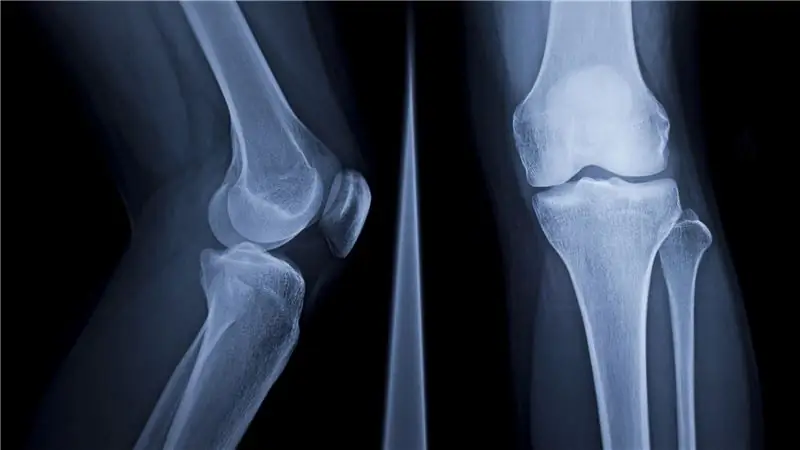

Если вы думали, что остеопороз - это проблема только женщин и пожилых мужчин, вы ошибались.

Извините, ребята, потеря костей сказывается и на вас. По словам доцента кафедры питания и физиологии упражнений Университета Миссури Памелы С. Хинтон, два миллиона американских мужчин могут иметь остеопороз, а еще 12 миллионов имеют низкую костную массу (также известную как остеопения).